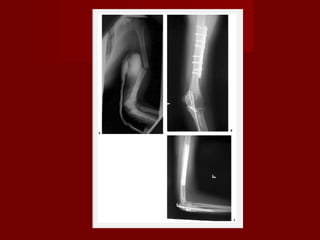

Osteosintese com placa Gold standard para fixação de fraturas de diafise do úmero Associado com uma alta taxa de consolidação, baixa taxa de complicação, retorno rápido da função. Pode ser usada em fraturas com extensão distal ou proximal É segura e efetiva em fraturas expostas. Complicações: paralisia do nervo radial(2 a 5%), infecção(1 a 2% fraturas fechadas e 2 a 5% em fraturas expostas) e refratura(1%)

Utiliza-se placas DCP ou LC-DCP largas de 4,5mm Em pacientes fisicamente pequenos podem ser utilizadas placas de 4,5mm finas Na zona de transição entre a diafise e a crista supracondilar pode-se utilizar 2 placas de compressão de 3,5mm uma na coluna medial e uma na coluna lateral Um parafuso interfragmentar utilizado através da fratura pode aumentar a rigidez entre 30 e 40%. Seis corticais proximais e distais com o uso de parafuso interfragmentario, se não for utilizado parafuso interfragmentario oito corticais proximais e distais Placas de bloqueio são artifícios novos, apresentando possível vantagem em fixação de ossos osteopenicos

Haste intramedular Hastes utilizadas anteriormente como pinos de Rush e hastes de Ender eram eficazes em fraturas simples, mas tinhas alguns problemas com instabilidade axial e rotacional Hastes novas com bloqueios, resolveram esses problemas, porém não apresentaram resultados tão bons como as hastes nas extremidades inferiores. Problemas com lesão no local de inserção, fraturas cominutas iatrogênicas e pseudoartrose foram observadas. Alem disso as vantagens das hastes como mobilidade precoce e diminuição de fraturas peri implantes foram ilusórias Estudos mostram uma taxa maior de reoperação e lesão de estruturas no ombro foram observadas. As indicações são fraturas patológicas, fraturas segmentar com grande diástase, lesão de partes moles

Estudos clínicos fixação com placas versus haste intramedular Dor no ombro muito menor em pacientes tratados com placas (0% com placas e 5 a 42% com uso de hastes anterógradas) Menor taxa de reoperação (6% com placas e 18% com hastes) Pseudoartrose (11% com hastes e 6% com placas)

Osteosintese com placaGold standard para fixação de fraturas de diafise do úmero Associado com uma alta taxa de consolidação, baixa taxa de complicação, retorno rápido da função. Pode ser usada em fraturas com extensão distal ou proximal É segura e efetiva em fraturas expostas. Complicações: paralisia do nervo radial(2 a 5%), infecção(1 a 2% fraturas fechadas e 2 a 5% em fraturas expostas) e refratura(1%)

Utiliza-se placas DCPou LC-DCP largas de 4,5mm Em pacientes fisicamente pequenos podem ser utilizadas placas de 4,5mm finas Na zona de transição entre a diafise e a crista supracondilar pode-se utilizar 2 placas de compressão de 3,5mm uma na coluna medial e uma na coluna lateral Um parafuso interfragmentar utilizado através da fratura pode aumentar a rigidez entre 30 e 40%. Seis corticais proximais e distais com o uso de parafuso interfragmentario, se não for utilizado parafuso interfragmentario oito corticais proximais e distais Placas de bloqueio são artifícios novos, apresentando possível vantagem em fixação de ossos osteopenicos

Haste intramedular Hastesutilizadas anteriormente como pinos de Rush e hastes de Ender eram eficazes em fraturas simples, mas tinhas alguns problemas com instabilidade axial e rotacional Hastes novas com bloqueios, resolveram esses problemas, porém não apresentaram resultados tão bons como as hastes nas extremidades inferiores. Problemas com lesão no local de inserção, fraturas cominutas iatrogênicas e pseudoartrose foram observadas. Alem disso as vantagens das hastes como mobilidade precoce e diminuição de fraturas peri implantes foram ilusórias Estudos mostram uma taxa maior de reoperação e lesão de estruturas no ombro foram observadas. As indicações são fraturas patológicas, fraturas segmentar com grande diástase, lesão de partes moles

Estudos clínicos fixaçãocom placas versus haste intramedular Dor no ombro muito menor em pacientes tratados com placas (0% com placas e 5 a 42% com uso de hastes anterógradas) Menor taxa de reoperação (6% com placas e 18% com hastes) Pseudoartrose (11% com hastes e 6% com placas)